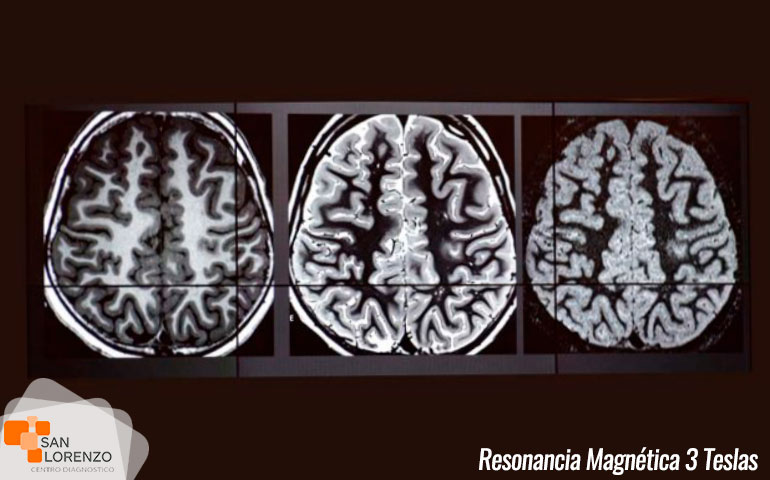

En simples palabras, una de las diferencias entre 1.5 Teslas y 3 Teslas en imagen médica, radica principalmente en la potencia de su campo magnético, lo que se traduce que mientras más elevado sean los Teslas, nos permite obtener información cada vez más detallada y sensible del cuerpo humano, mejorando el diagnóstico a cada paciente y aportando a médicos radiólogos y especialistas información más precisa sobre una enfermedad determinada.

Centro de diagnóstico San Lorenzo, gracias a la mejora continua a nivel de tecnología en imágenes, cuenta actualmente con un resonador magnético General Electric de 3 teslas, uno de los únicos resonadores de estas características en la región de O’Higgins y zona centro sur, que permite el diagnóstico de diversas patologías como tumores, cáncer y otras enfermedades cada vez más comunes y complejas, permitiendo este estudio el acceso a todos los habitantes de Rancagua a Punta Arenas.